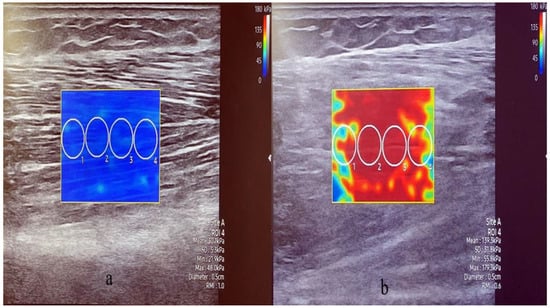

Bモード(2次元超音波画像表示)を用いて断面で測定した。その後、プローブを筋繊維の方向に回転させ、SWEモードを使用して縦断面の静止筋硬度および収縮筋硬度を取得した。筋厚は、表層部と深層部の腱膜の距離として測定した。

筋スティフネスについては、円形の関心領域は直径5mmで、筋線維に平行に配置。局所的な貫通欠損や線維性隔壁は避けた。各 SWE 画像に 4 つの関心領域の円を作成し、剛性値の平均を算出した。値はPkaで記録された。筋厚と剛性は同じ位置から取得した。